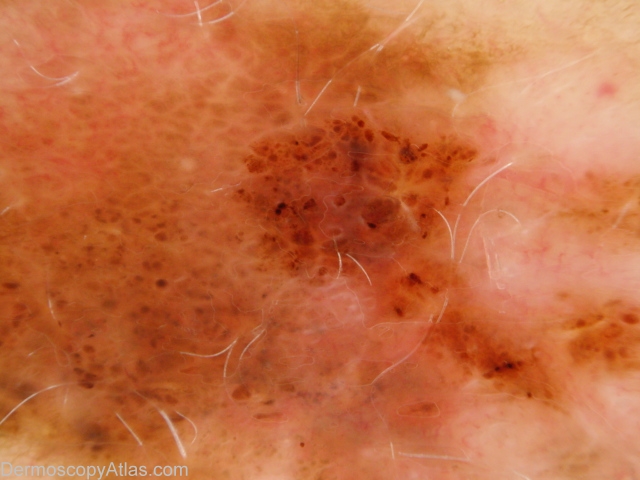

Site: Abdomen

Diagnosis: Melanoma invasive

Sex: F

Age: 54

Type: Dermlite Polarised

Submitted By: Ian McColl

Description: Pigmented lesion on the back showing pigment dots, asymmetry of pigmentation and a negative network.

History: This lesion had developed over several months. It was brought to her attention by being itchy. It was a superficial spreading melanoma, 0.35mm thick , Clark level 2. The histopathology did show some features of regression.